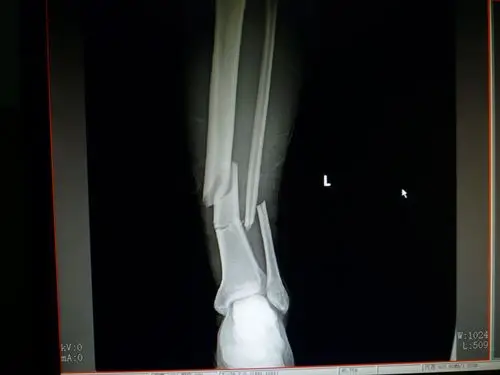

三例胫腓骨远端骨折